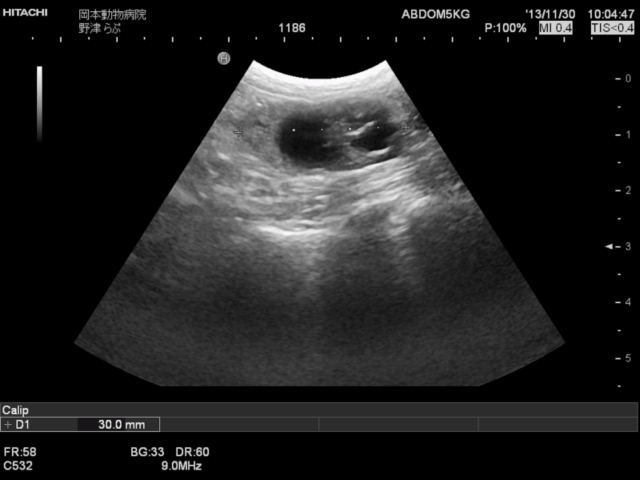

その結果、あちらこちらに異常所見が見つかりましたが、最も重要な所見として卵巣の異常を指摘しました。

そして手術となったわけですが、腹腔内には血様腹水があり卵巣はもちろん、膀胱・腹膜まで播種(細かな転移巣)が見られました。

卵巣は病理検査の結果卵巣がんということでしたので、予後不良と判断したのですが、こちらの意に反して犬は術後すこぶる元気となり食欲も旺盛となりました。